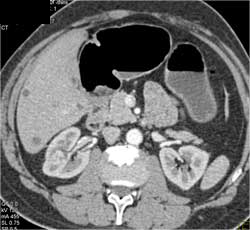

Transitional Cell Cancer (TCC) of Right Kidney